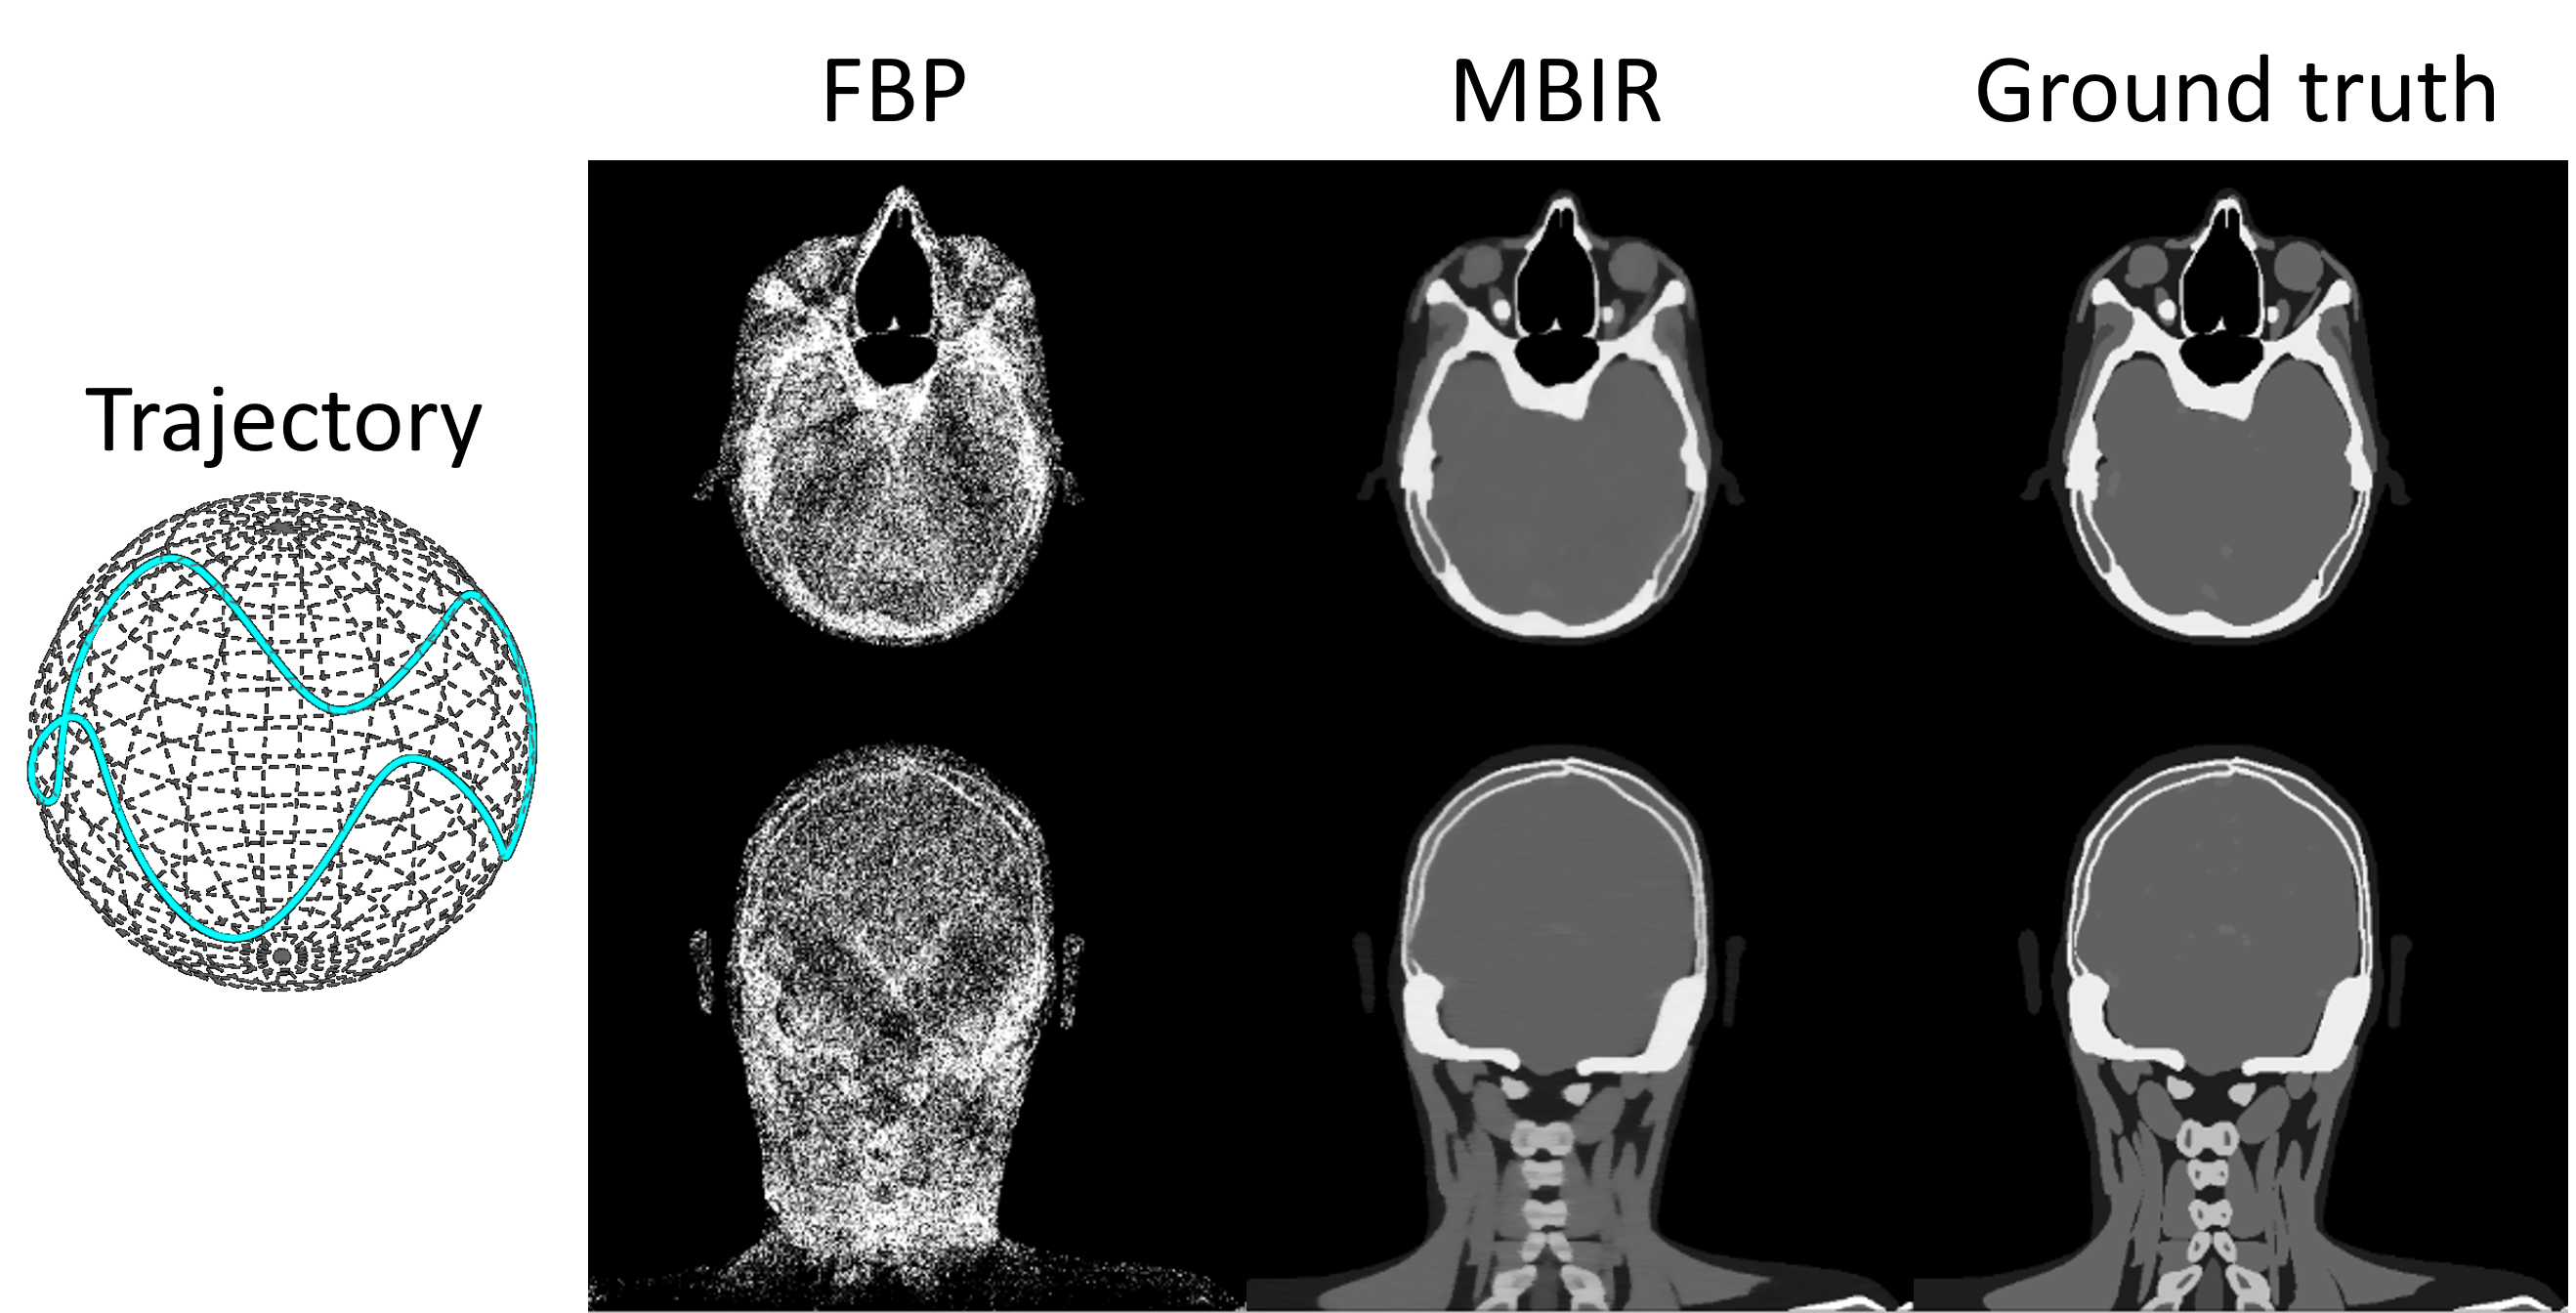

Finally, we validate the effectiveness of auto-differentiation through MBIR. As illustrated in Fig. 7, 200 head[24] cone-beam projections are simulated with a sinusoidal scan trajectory. The objective function of MBIR is formulated as:

x=argminxAxy22+λxTV\textbf{x}^{*}=\text{argmin}_{\textbf{x}}\|\textbf{Ax}-\textbf{y}\|_{2}^{2}+\lambda\|\textbf{x}\|_{TV} (3)

The objective function is minimized with 200 iterations of the Adam optimizer where the gradient is computed via auto-differentiation (as shown in the Sec.2.4). Due to the irregular projection sampling pattern, FBP reconstruction exhibits substantial non-uniformity. In contrast, MBIR effectively improves the reconstruction accuracy, as evidenced by a clear depiction of bone and soft tissue boundaries. These results validate the effectiveness of auto-differentiation in conjunction with the CTorch projector.

Refer to caption

Figure 7: FBP and MBIR reconstruction of projections simulated with a non-circular scan trajectory.